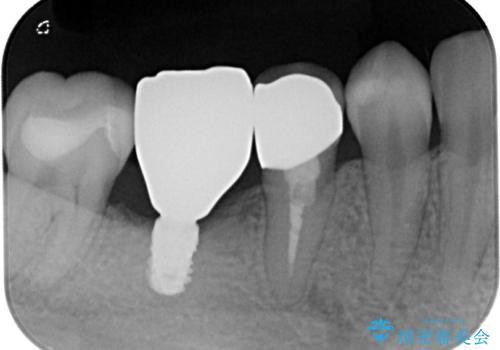

- インレーブリッジをインプラントにやり替えて銀歯を白くしたいとのことで来院された患者様です。

既に抜歯をして歯のない箇所にはインプラント治療をし、ブリッジの土台となっている歯のうち、手前側の小臼歯は既に根管治療をされている歯なのでオールセラミッククラウンへのやり替え、奥側の大臼歯はセラミックインレーへのやり替えをしていくこととしました。

根管治療のやり直しは希望されなかったため、土台の部分からのやり替えです。